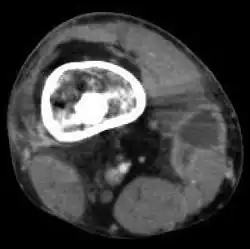

Osteomyelitis

| Osteomyelitis of the 1st toe | |